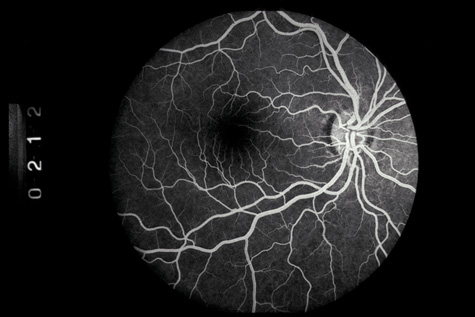

SCLERAL RUPTURE

In eyes that have not undergone prior surgery, the two most common locations for scleral rupture are at the limbus (under intact conjunctiva) and parallel to the muscle insertions between the insertion and the equator. Radial and posterior ruptures are relatively uncommon.29

The hallmarks of scleral rupture are severe reduction in visual acuity, an afferent pupillary defect, hypotony (although a normal intraocular pressure does not rule out a small rupture), an abnormally deep anterior chamber, decreased ocular ductions, severe subconjunctival edema (Fig. 24), hyphema, and vitreous hemorrhage.92 The diagnosis can rarely be confirmed by ophthalmoscopy because severe vitreous hemorrhage, hyphema, or both nearly always accompany scleral rupture. Ultrasonography and computed tomography (CT) scanning may be helpful. Both show a shrunken globe. In addition, the CT scan shows subconjunctival edema (Fig. 25). In eyes in which the anterior chamber depth cannot be seen because hyphema, ultrasonography and CT scanning often show a deepened chamber. CT scanning is also useful in identifying any intraocular foreign bodies.

Fig. 25. Computed tomography of a patient with a ruptured globe demonstrates severe subconjunctival edema and a collapsed globe.